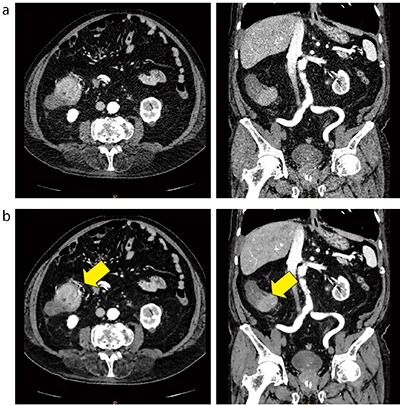

IMR Platinumは,先に述べたとおりVirtually Noise-Free Imagingによる最大90%のノイズ低減が可能であり,従来の逐次近似応用画像再構成法ではノイズ除去が困難であった体格の大きい患者の低管電圧撮影においても有用である(図5)。

図5 IMR Platinumを用いた低管電圧撮影

80kV,811mAs,CTDIvol:15.9mGy

従来の逐次近似応用画像再構成法iDose4(a)とIMR Platinumの比較(b)(いずれも1mmスライス,患者体重90kg,eGFR:44.6)。IMR Platinumのノイズ低減により,上行結腸がん内部に走行している血管(←)が描出されている。